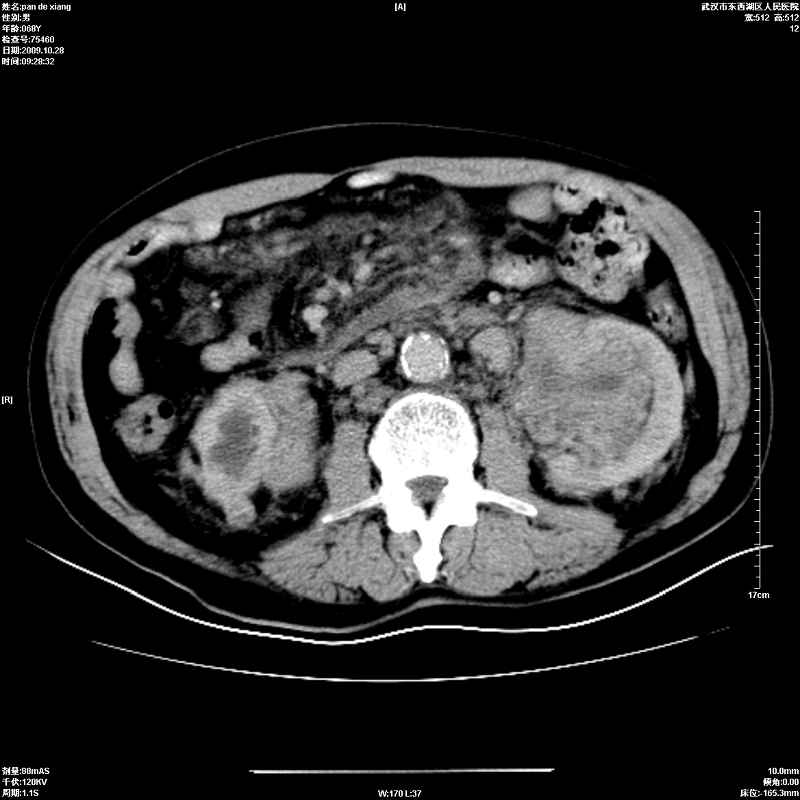

以下是引用杀毒软件在2009-10-28 20:41:00的发言:[br]结合临床考虑---白血病双肾改变或淋巴瘤。

以下是引用zxl51642在2009-10-29 9:59:00的发言:[br]结合临床“单克隆免疫球蛋白血症”,考虑双肾为继发损害并肾功能不全(尿中大量igg及少量iga、igm等大分子免疫球蛋白滤出所致继发损害),椎前软组织肿块为髓外造血。与浆细胞瘤有区别,平扫时有战友说的很清楚。